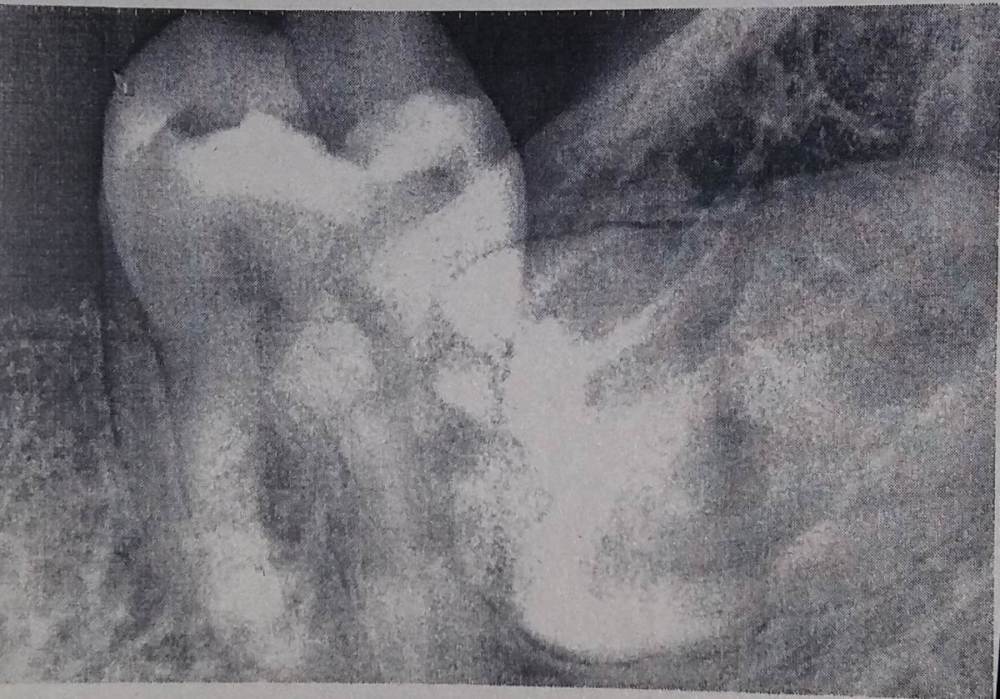

Андрей_Г Опубликовано 3 марта, 2023 Поделиться Опубликовано 3 марта, 2023 (изменено) Здравствуйте! У меня уже неделю болит десна и вздулась щека, ходил в платную стоматологию к стоматологу-терапевту. Думал, что флюс. Я прочитал про признаки перикоронарита, совпадало. Стоматолог осмотрела ротовую полость, проверила, почему то с 28 летним стажем не удивило ее изменение цвета десны и припухлости на ней. Возможно устала, так как я вечером ходил. Спросила, где болит, я показал что десна, я сказал может зуб мудрости растет. Сходили на рентген сделала снимок, горизонтальный зуб мудрости(8) упирается в моляр(7) 1. Сложная будет операция с этим зубом? 2. Пилить нужно будет и/или долбить и/или дергать зуб? 3. Какие противоспалительные средства можно пить? Ибупрофен пока пью. Нужно ли пить антибиотики: амоксоциллин например? 4. Сколько времени еще можно не обращаться за помощью к хирургу, если прошла уже неделя? В нашем городе пара хирургов-стоматологов с большим стажем 15 лет. Хотелось бы попасть к хорошему специалисту, так как начитался и долгого 2 часовых изнурительных манипуляций(сверление, пиление, долбление и т.д.) и наложение 12 швов, сломанной кости челюсти, многих побочных эффектов. Я думаю, в этом деле особенно от квалификации зависти результат хирурга-стоматолога, у того к которому хочу записаться, за неделю надо вставать в очередь. Снимок пришлю Благодарю за ответ! Изменено 3 марта, 2023 пользователем Андрей_Г Ссылка на комментарий

Irouil Опубликовано 3 марта, 2023 Поделиться Опубликовано 3 марта, 2023 На мой взгляд, этот зуб (лежащий) практически не может быть причиной опухания десны и/или абсцесса. К глазу он отношения точно не имеет 1 1 Ссылка на комментарий

Irouil Опубликовано 4 марта, 2023 Поделиться Опубликовано 4 марта, 2023 Конечно, томография не помешает, точное соотношение зуба с критически важным нижнечелюстным каналом перед удалением может повлиять и на тактику, и на безопасность, и на общий комфорт операции. Ссылка на комментарий